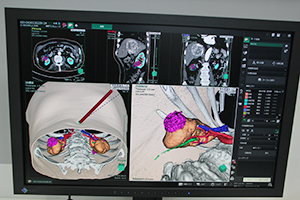

ITコーナーでは,3D画像解析システム「SYNAPSE VINCENT」の最新のバージョン4のソフトウエアを中心に展示した。泌尿器科領域での腎臓の腹腔鏡下手術シミュレーション,頭部の神経線維や血管などを表示した開頭手術シミュレーションなどのほか,モバイル端末への対応などをアピールした。そのほかSYNAPSEの新機能として,画像認識技術を使った骨ラベリング,肝臓がんに対応したSYNAPSE CaseMatchなどを紹介した。

SYNAPSE VINCENTの新しいソフトウエアを紹介。泌尿器科領域での腎臓の腹腔鏡下手術シミュレーション

神経線維や血管の情報を表示した脳腫瘍などの開頭手術の術前シミュレーション